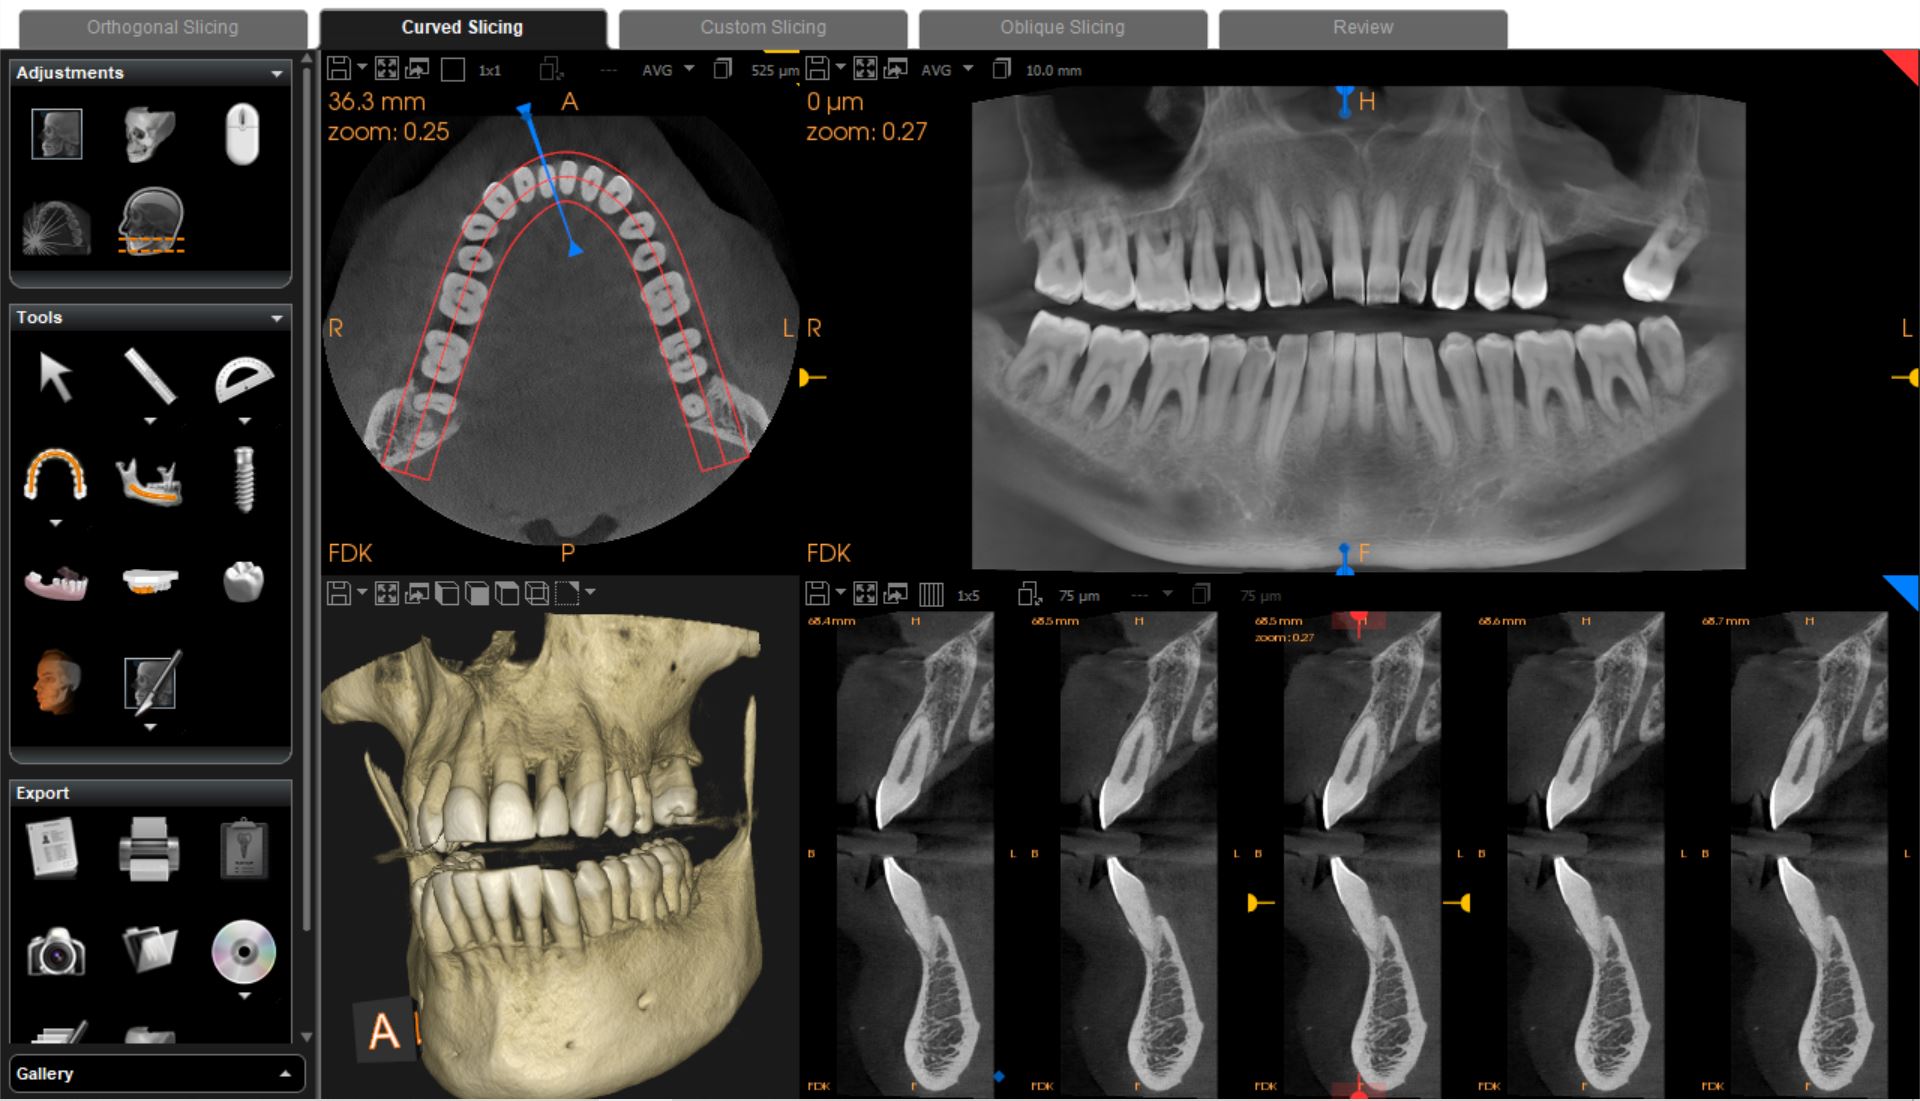

Το νέο μοντέλο CS 8200 3D Neo Edition της Carestream Dental συνδυάζει Ψηφιακή Πανοραμική με Ογκομετρικό Τομογράφο CBCT, με επιλογή εννέα οπτικών πεδίων και ανάλυση έως 75μm.

Με νέο εύχρηστο λογισμικό και ακόμα μεγαλύτερες δυνατότητες όπως το CS MAR, αλγόριθμος NAR, ανατομικά φίλτρα Endo, Perio,τεχνολογία Tomosharp, το καθιστούν ως το πιο κατάλληλο μηχάνημα για Οδοντιατρεία και Διαγνωστικά κέντρα καλύπτοντας όλο το φάσμα των απεικονίσεως οδοντογναθοπροσωπικής περιοχής με πεντακάθαρες εικόνες.